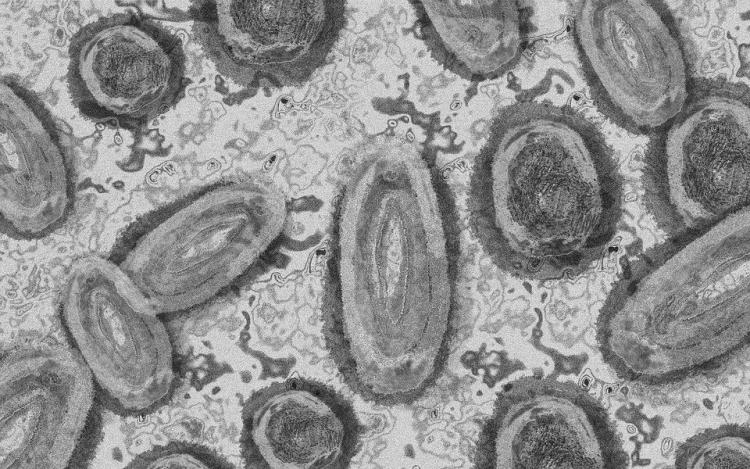

Újabb kilenc, 23-50 éves férfinél igazolták a majomhimlő-fertőzést Magyarországon, ezzel 42-re nőtt a fertőzöttek száma - közölte a Nemzeti Népegészségügyi Központ (NNK) csütörtökön az MTI-vel.

A betegség általános, nem specifikus tünetekkel - lázzal, hidegrázással, izomfájdalommal, hátfájdalommal, fejfájással, fáradtsággal), illetve a nyirokcsomók duzzanatával kezdődik, majd 1-3 nappal a bevezető tünetek után bőrkiütések jelennek meg. A kiütések sok esetben először az arcon, majd a tenyéren és a talpon fordulnak elő, de megjelenhetnek a szájnyálkahártyán, a nemi szerveken és a végbél környékén is - olvasható a közleményben.